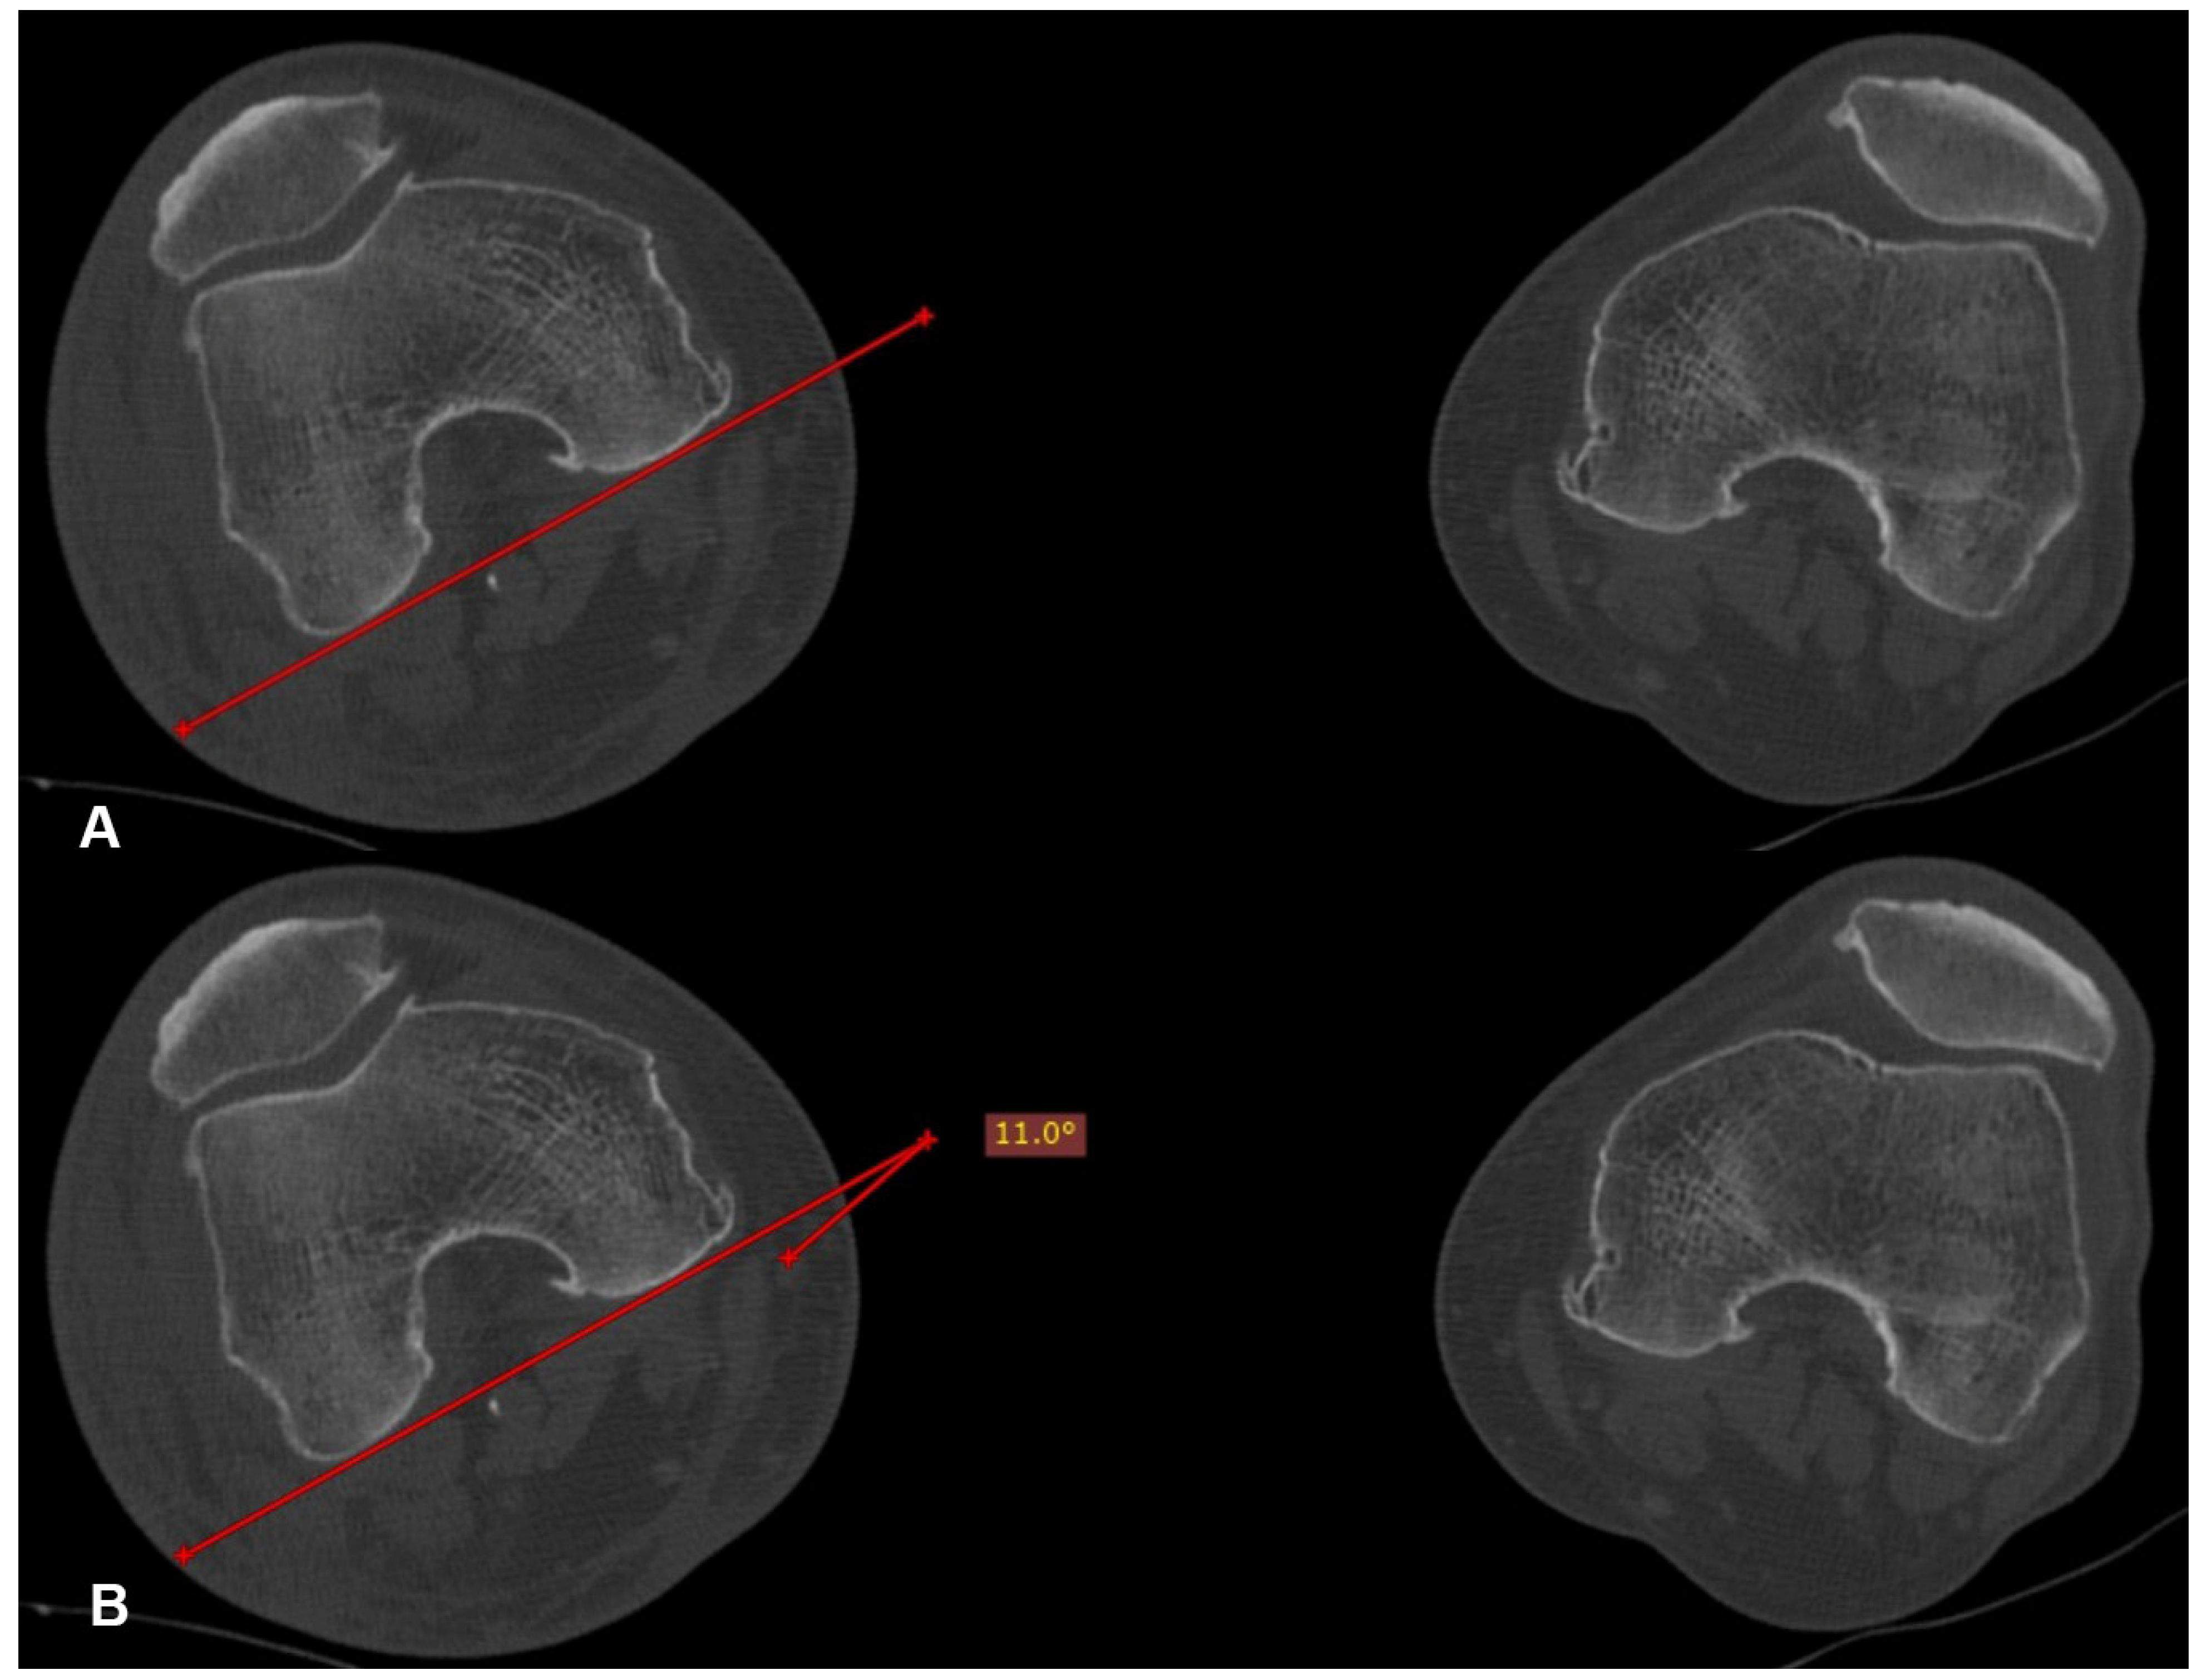

Postoperatively, all of the patients underwent a CT scan of pelvis-hips and knees, if they were willing to and when they felt comfortable. On the CT scan, the anteversion of both the operated (angle 1) and the healthy (angle 2) hip was measured for every patient. The preferred method used for these measurements was the one suggested by Jeanmart et al. in 1983 [6] (Figure 2, Figure 3 and Figure 4). The difference (D angle) between the anteversion of the operated hip and the healthy hip was calculated. A D angle with a positive value indicated internal over-rotation of the distal fragment during reduction, while a D angle with a negative value indicated external over-rotation, respectively. The absolute value of the D angle represented the difference in hip anteversion.

Figure 4. Tangent line to the posterior femoral condyles in the transverse section where they present the maximum anteroposterior diameter (A). Projective angle formed between the tangent line at the posterior femoral condyles and the line connecting the center of the head with the center of the neck. This angle expresses the femoral anteversion (B).